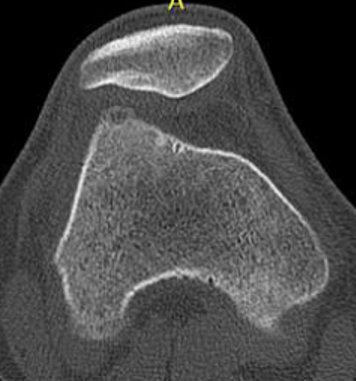

CT

Best investigation

- lucent nidus surrounded by dense bone

Osteoid osteoma femur